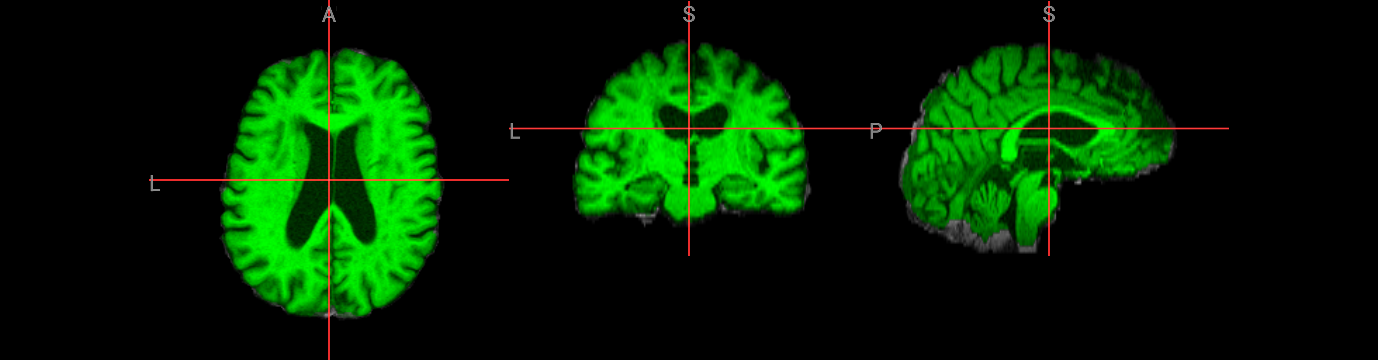

Brain extraction is a fundamental preprocessing step in neuroimaging analysis, particularly critical for structural image segmentation where precision matters most. While BET is straightforward to use, achieving optimal results often requires understanding how to fine-tune parameters for challenging datasets. This interactive version covers the core BET fundamentals, including parameter adjustment techniques for difficult images, and troubleshooting approaches for problematic cases. The hands-on format allows you to experiment with different settings and immediately see their effects on brain extraction quality.